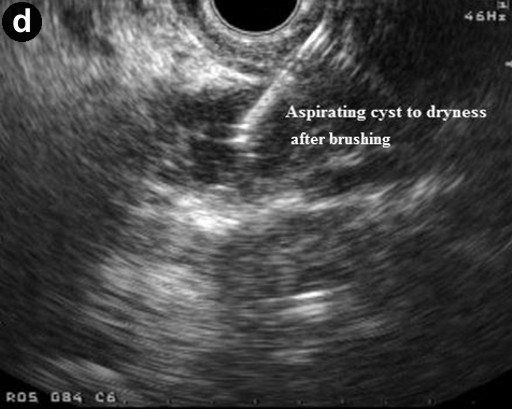

All patients had platelet count and coagulation profile checked and corrected if needed prior to the procedure. Procedures were done under intravenous sedation with diazepam and pethidine or midazolam and fentanyl. Cyst sampling was done by two operators with a combined experience of over 1,000 linear EUS procedures (GPA and KR). The lesion was identified and punctured using a 19 G needle using curvilinear echoendoscope (GF-UCT240-AL5, Olympus KeyMed, Essex, United Kingdom) and 50% of the cyst content was initially aspirated. The echobrush (Cook Medical, Limerick, Ireland, United Kingdom) was then passed through the handle and advanced through the needle till the whole brush could be visualised in the cyst. The wall of the cyst was then brushed by to and fro movement of the brush tip by moving the shaft of the needle at the handle. The opposite wall of the cyst was then visualised by moving the handle of the scope sideways and the brushing repeated at least four times (Figure 1). The brush was targeted if septae or nodules were present on the cyst wall. The brush was pulled back into the needle tip prior to removing the needle from the cyst and the needle apparatus with echobrush was withdrawn as a whole. The cyst was then aspirated to dryness using either a 19 G or 22 G needle. In patients where only FNA was done the cyst was punctured and aspirated using a 22 G needle.

Figure 1. Linear endoscopic ultrasound showing EUS-guided brushing of a cystic pancreatic lesion. a. EUS-FNA 19 G needle entering a cystic lesion in the head of the pancreas. b. The cyst being aspirated. c. The cyst wall being brushed by echobrush introduced through the needle. d. The cyst aspirated to dryness after cyst wall brushing. |